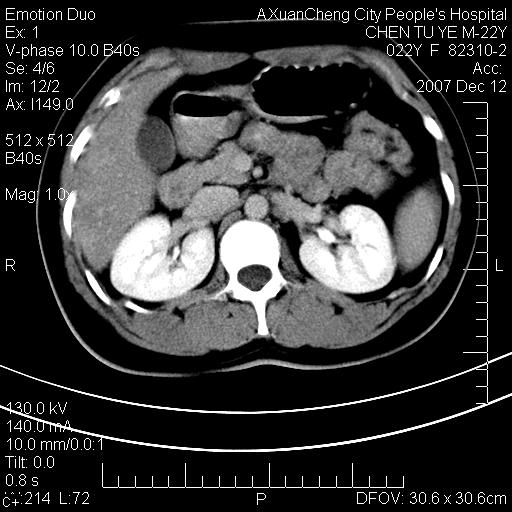

超声提示肝右前叶占位,约2.5cm.

各位战友看看病灶在什么地方,可是右前叶进肝裂部低密度影,平扫ct值约10以下,增强后增高明显

1 脾大,慢性肝损伤. 2 肝脏脂肪侵润.  3 你所指的部位疑点,我没看出有问题.

脂肪肝,脾大

重度脂肪肝.